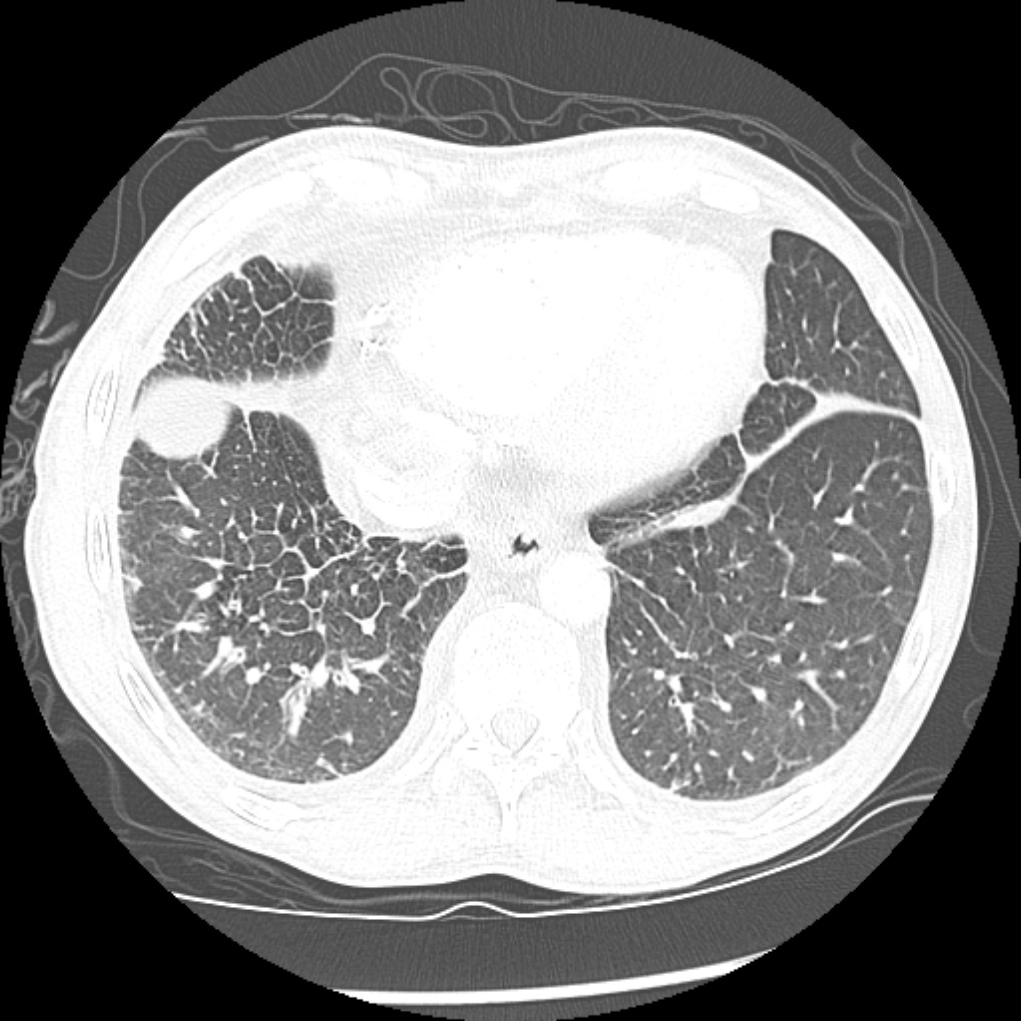

Round Atelectasis

Focal atelectasis with a round morphology that is always associated with an adjacent pleural abnormality (e.g. pleural effusion, pleural thickening or plaque, pleural neoplasm, etc). Round atelectasis is most common in the posterior lower lobes. All five of the following findings must be resent to diagnose round atelectasis: 1. Adjacent pleura must be abnormal. 2. Opacity must be peripheral and in contact with the pleura. 3. Opacity must be round or elliptical. 4. Volume loss must be present in the affected lobe. 5. Pulmonary vessels and bronchi leading into the opacity must be curved, this is the comet tail sign.